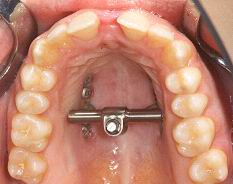

Modern therapy methods, such as distraction osteogenesis, are routinely used and also represent a research focus of the clinic (Magdeburg Palatal Distractor).